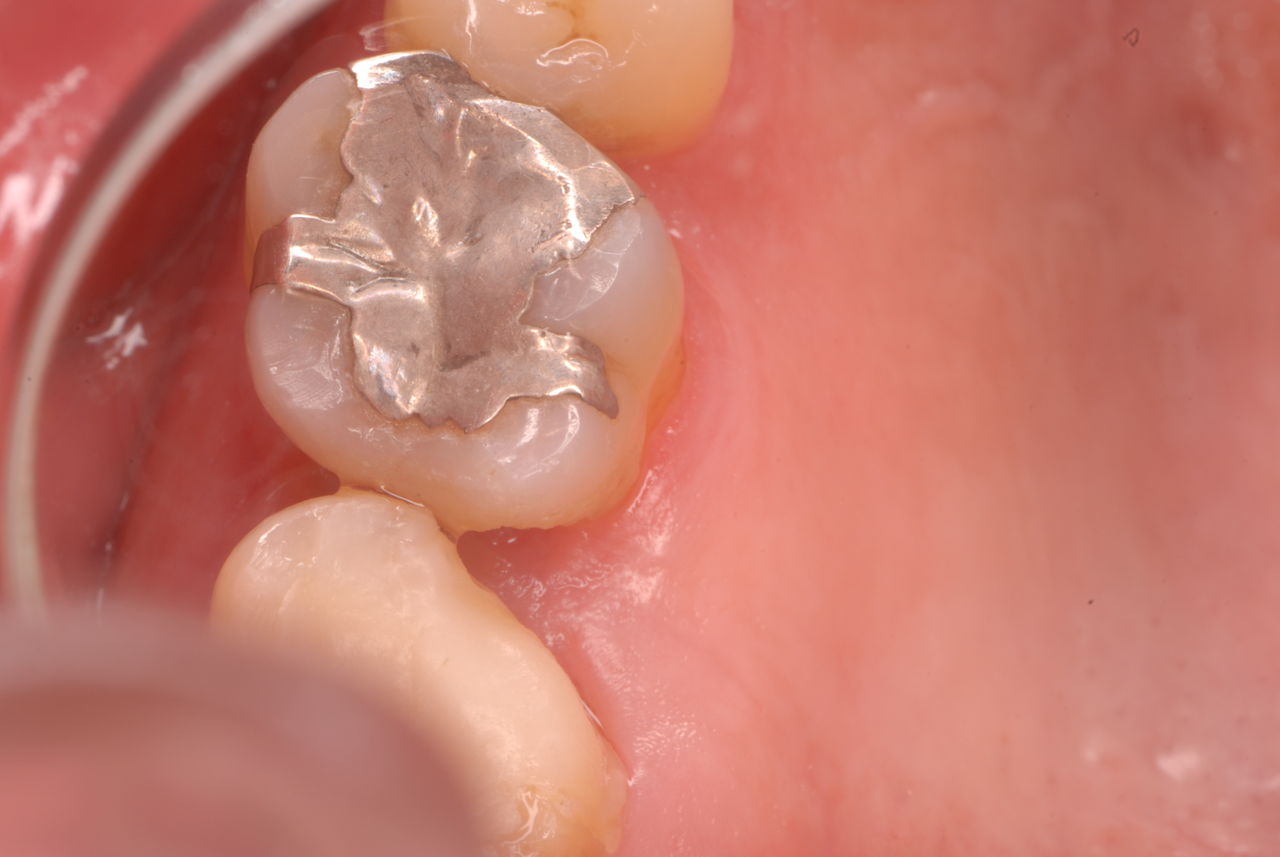

ご自分でやられても歯茎から血が出ないと話をされていましたが、私がブラシを当てると悲惨な状態であることがわかりました。

何故歯が悪くなるのか、歯周病で抜けるのか分からなければ何を入れても歯は悪くなり抜けていくのです。

病気を治しましょう。それから差し歯や入れ歯を入れましょう!物を入れれば入れるほど、磨き方や掃除の仕方が上手にならなければ、すぐ抜けてくるのです。